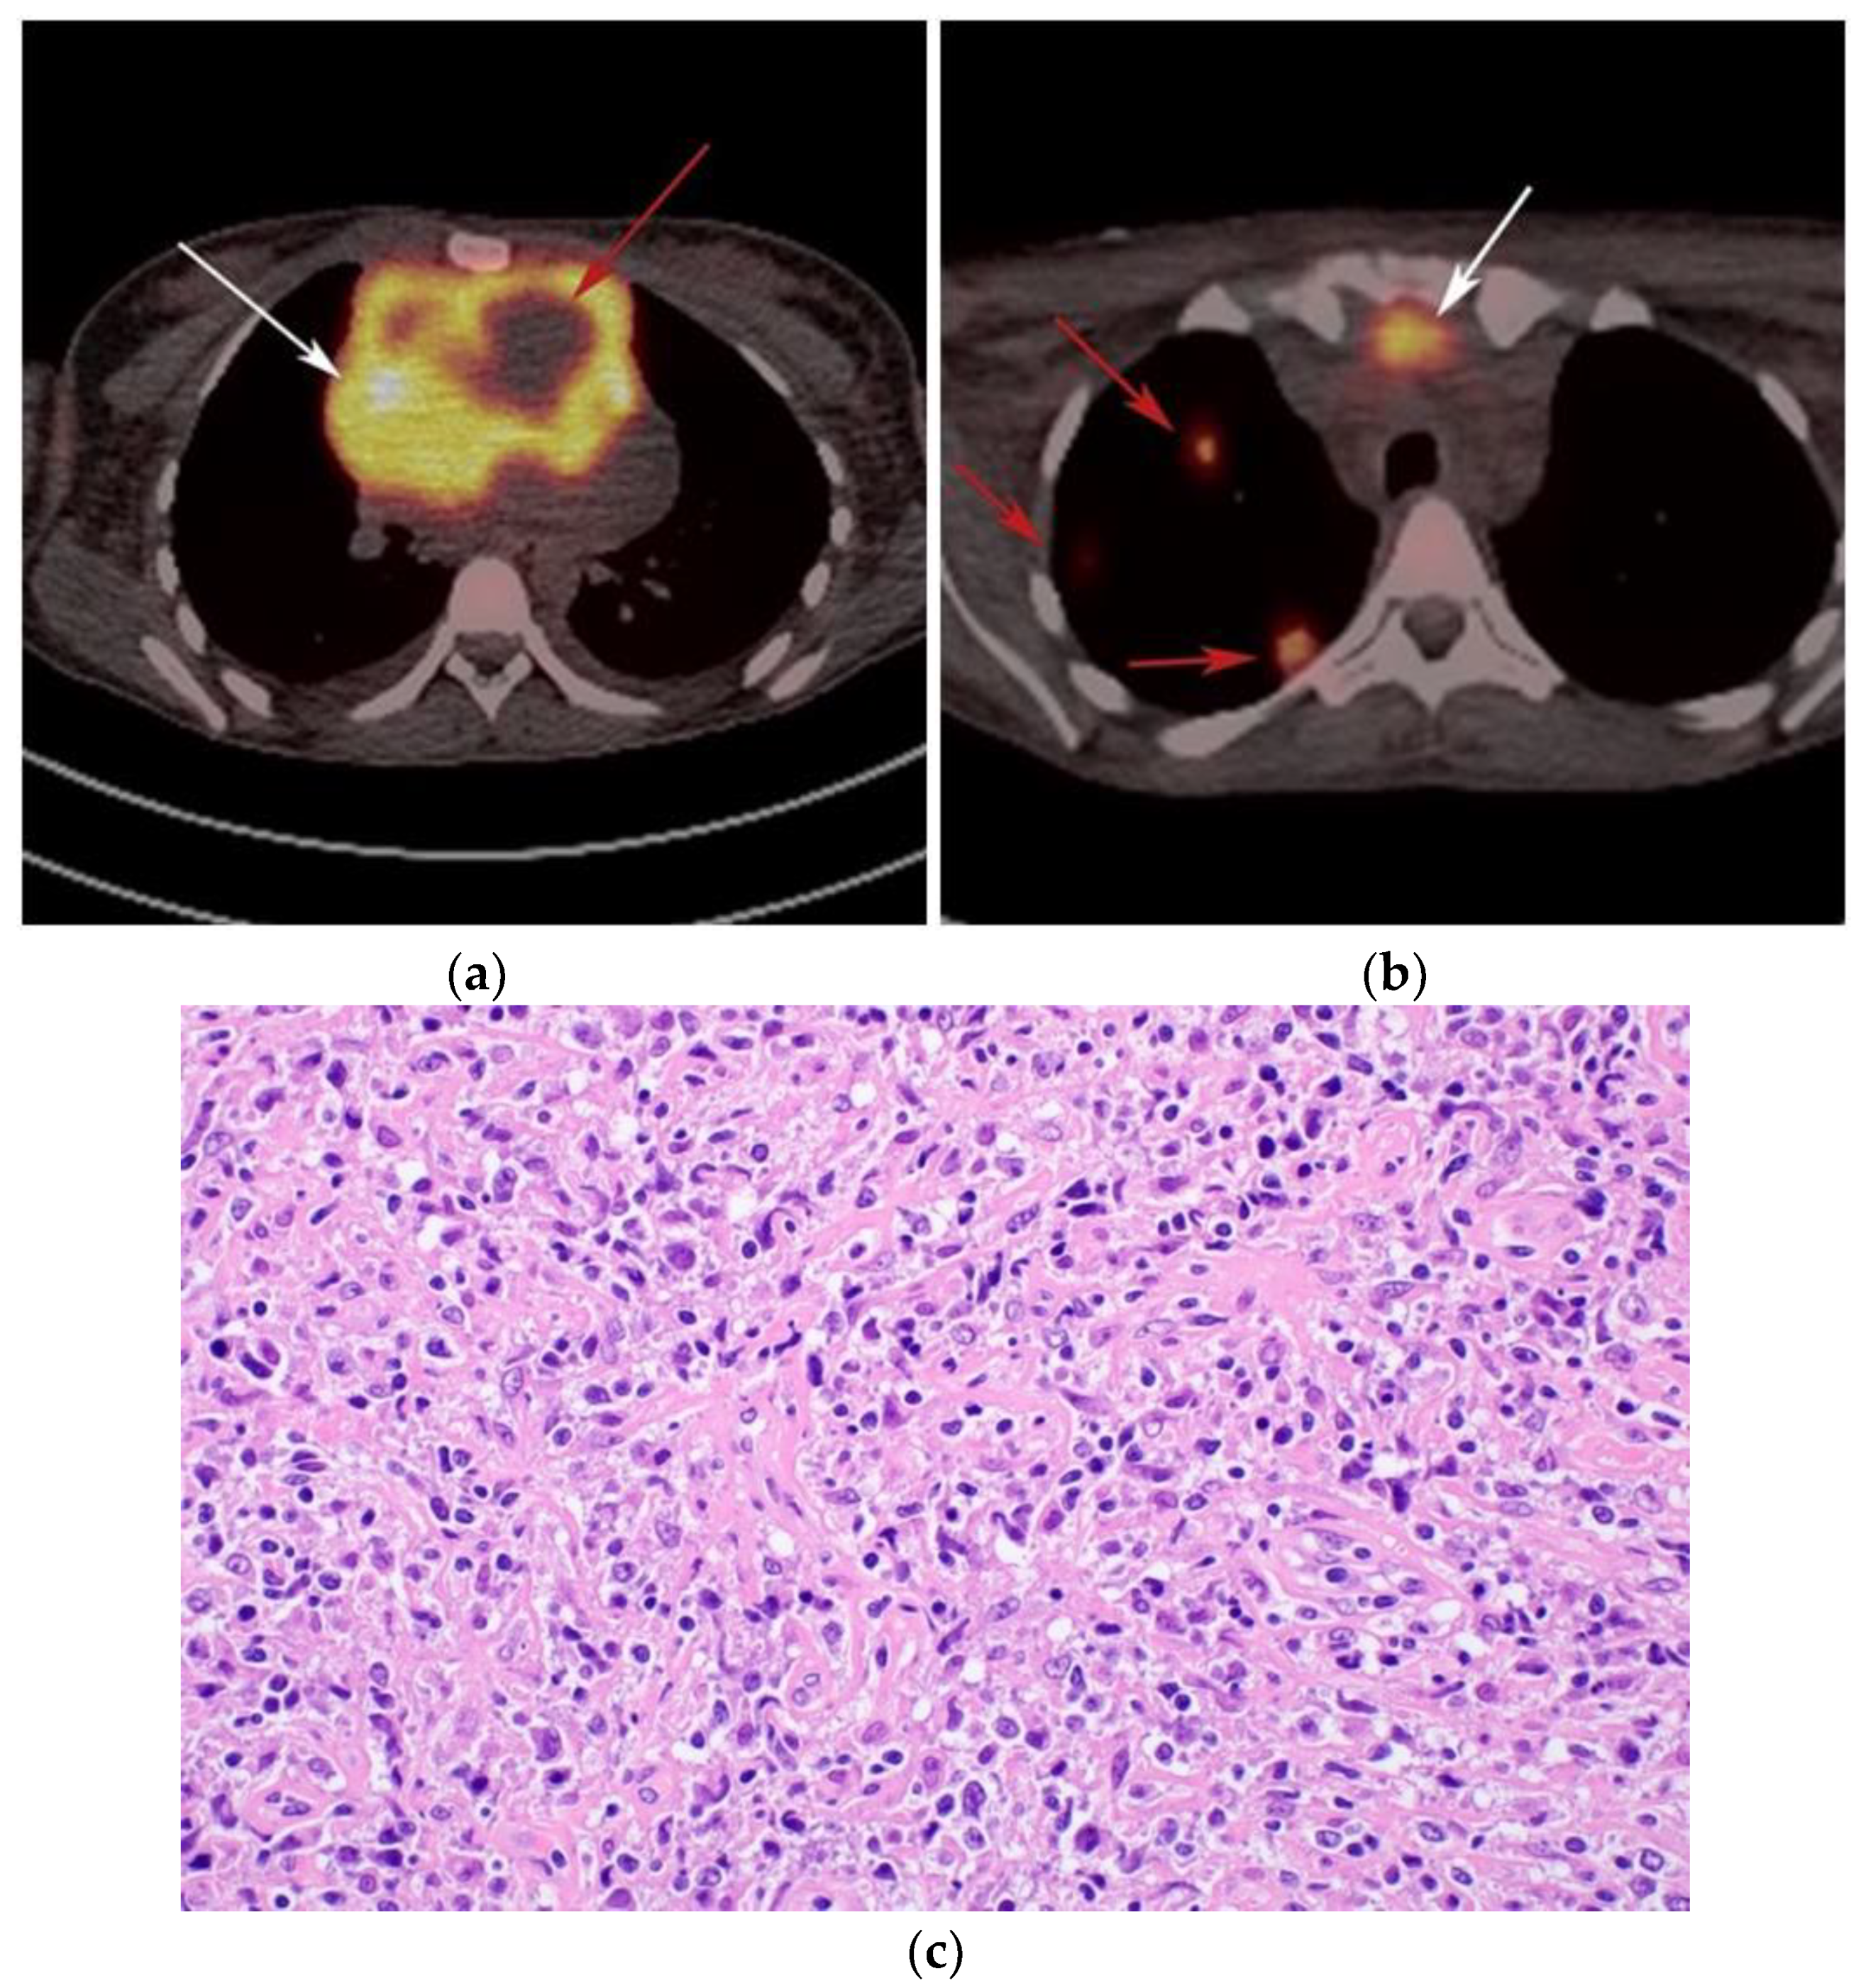

The differential diagnosis of PMLBCL includes other anterior mediastinal masses such as CHL, germ cell tumors, and large thymic tumors, which can display necrosis and calcifications on CT [32]. Differentiation between PMBCL and CHL is not possible based on imaging findings alone. More aggressive clinical behavior such as superior vena cava syndrome may help distinguish PMBCL from CHL [33] (Figure 5).

The use of 18F-FDG PET/CT is essential in the evaluation of patients with PMLBCL to reveal sites of disease not visible on CT and to provide more accurate staging and radiation field planning (Figure 6). 18F-FDG PET/CT may also be beneficial for restaging after chemotherapy and/or radiotherapy, or when relapse is suspected [34]. Negative 18F-FDG PET/CT after two or four cycles of chemotherapy has a negative predictive value and may predict excellent outcome in patients, achieving complete response without relapse. Patients who have residual activity equal to or higher than liver activity after immunochemotherapy treatment are more likely to relapse. In such instances, the addition of radiotherapy to the treatment regimen should be considered to avoid relapse in those high-risk patients. Relapse usually occurs within 1 year and is more likely to be widespread, involving distant extranodal sites such as the CNS, liver, kidneys, adrenal glands, GI tract, ovaries, and pancreas. Late relapses are very uncommon [35]. 18F-FDG PET/CT can also efficiently assess post-treatment response, differentiating between necrotic or fibrotic tissue and residual masses containing viable tumor [33,36]. There are various potential challenges to 18F-FDG PET/CT post-treatment implementation, including false-positive results secondary to thymic rebound hyperplasia, specifically seen in the young population. This can be limited by increasing the interval between treatment and imaging. Additionally, MRI can be helpful in those cases, and high signal on T1 in phase imaging with loss of signal on the out of phase sequences is consistent with thymic rebound hyperplasia (Figure 7 and Figure 8) [34,37].

Figure 6.

Imaging in a different patient with known diagnosis of primary mediastinal B-cell lymphoma. (a) Axial FDG PET/CT images show the hypermetabolic anterior mediastinal mass (white arrows), and there is also central areas of absent metabolic activity within the mass (red arrow), correlating with areas of fibrosis, a finding that is essential in prebiopsy planning to avoid false negative results. (b) Axial FDG PET/CT images show hypermetabolic right upper paratracheal nodes (white arrows) and several additional hypermetabolic pulmonary and pleural-based nodules within right upper lung (red arrows). (c) H&E section shows that the tumor is composed of large, atypical cells with reniform or multi-lobulated nuclei with abundant clear cytoplasm. Note the lymphoma cells are compartmentalized by the prominent sclerotic bands of fibrosis. (Original magnification 400x, H&E stain).